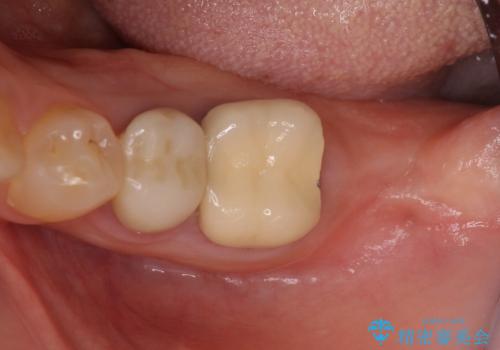

- 抜歯が必要と診断された奥歯の治療を希望して来院された患者様です。

一番奥の歯は歯根の一部を残した状態で、手前の歯とブリッジが装着されていました。